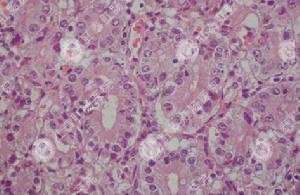

福州医博肛肠的医生介绍说,慢性肠炎对身体危害非常大,往往会引起慢性腹泻的慢性肠炎与精神紧张、消化不良、肠功能混乱、免疫功能失调、肠抵抗力下降有关,造成肠道粘膜炎症、溃疡。该病病程较长,反反复作,老少均有发生,严重影响人类健康。

慢性肠炎的治疗需先肠镜检查

在对肠炎的治疗上,福州医博肛肠医院有其特色治疗方法。借助先进的超细肠镜,可患者检查时舒适、苦,通过高清晰医用视频方法,对自乙状结肠至升结肠一百多厘米的整个大肠细微病灶均可清晰检查,连毛细血管也看得清清楚楚,杜绝误诊、漏诊,率高达99.9%以上。